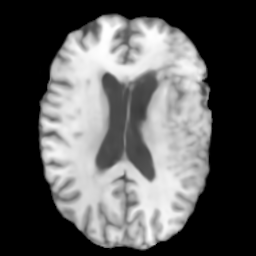

Brain MRI

We also evaluate our method on the BraTS-Reg (Baheti et al. 2021) dataset, which provides pre-operative and follow-up MRI scans for patients with diffuse glioma. The dataset includes multimodal MRI sequences (T1, T2, FLAIR, and T1 contrast-enhanced) collected longitudinally for each subject. To mitigate inter-scan variability caused by different acquisition protocols, histogram standardization (Nyul, Udupa, and Zhang 2000) is first applied to the pre-operative and follow-up T1 and T2 scans. We then perform Z-normalization, rescale the intensity to the range, and crop the scans to a resolution of . The pre-operative and follow-up scans are rigidly aligned using the SimpleITK registration framework (Yaniv et al. 2018). For experiments, 160 subjects in BraTS-Reg are split into training and testing sets with a 7:3 ratio and the central eleven slices are extracted to form a dataset with 1232 training pairs and 528 testing pairs.

4.5 Experiment Results on Brain MRI

To further demonstrate the effectiveness of TraceTrans, we additionally evaluated the model on Brain MRI dataset. The quantitative results are shown in Table 2 and TraceTrans performs best in SSIM, MAE, NMI and slightly worse than MUNIT in PSNR. Since the difference between TraceTrans and MUNIT on PSNR is less than 5% of either standard deviation, then this difference is negligible. TraceTrans shows significant SSIM improvement while matching MUNIT’s PSNR and achieving the lowest MAE, demonstrating balanced excellence in both structural and textural translation. Qualitative results are illustrated in the second row of Figure 4, the image generated by our model is visually best similar to the reference image.